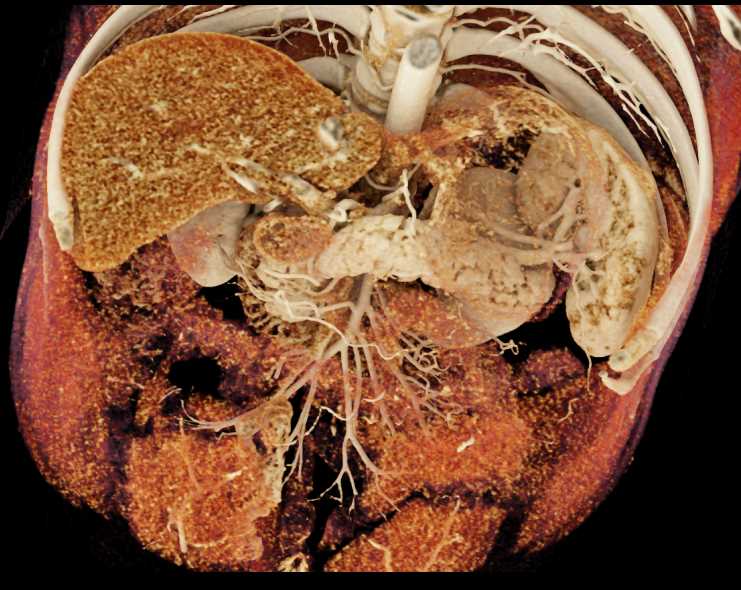

Subtle Neuroendocrine Tumor Body of Pancreas